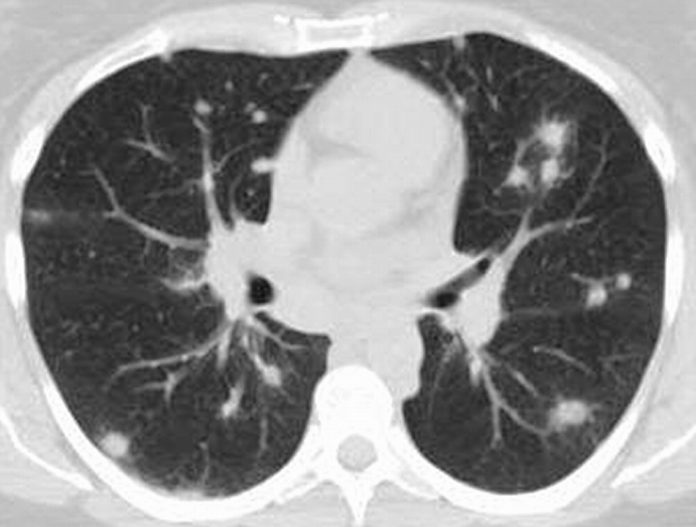

Η ακτινογραφία θώρακος δείχνει λεμφαδενοπάθεια με αποτιτανώσεις στο μεσοθωράκιο.

Αποτιτανώσεις στους πνεύμονες, τη σπλήνα και το ήπαρ, περικαρδίτιδα, πλευρίτιδα ή πλευριτική συλλογή.

Η ινώδης μεσοθωρακίτιδα προκαλεί στένωση των βρόγχων και των αγγείων του μεσοθωρακίου με αποτέλεσμα πνευμονική υπέρταση, σύνδρομο άνω κοίλης φλέβας και βρογχική απόφραξη.